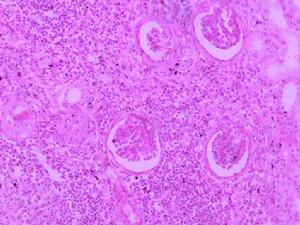

氟羅沙星治療案例-腎盂腎炎的治療

腎盂腎炎

腎盂腎炎的雙手一般治療目的在於緩解症狀,防止復發,減少腎實質的損害。應鼓勵患者多飲水,勤排尿,以降低髓質滲透壓,提高機體吞噬細胞功能,沖洗掉膀胱內的細胞。通常應鼓勵患者多飲水、勤排尿,以降低髓質滲透壓,提高機體吞噬細胞功能。有發熱等全身感染症狀應臥床休息。服用碳酸氫鈉1g,每日3次,可鹼化尿液,減輕膀胱刺激刺激症狀,並對氨基糖甙類抗生素、青黴素、紅黴素及磺胺等有增強療效作用,但可使四環素、呋喃咀啶的藥效下降。有誘發因素者應治療,如腎結石、輸尿管畸形等。抗感染治療最好在尿細菌培養及藥物敏感試驗下進行。